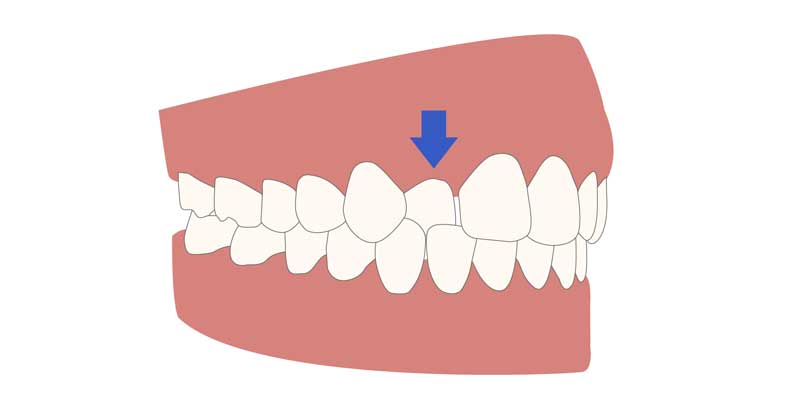

- کراس بایت قدامی (جلویی): در این حالت، یکی یا چند دندان جلویی فک بالا هنگام بسته شدن فک ها، پشت دندان های فک پایین قرار می گیرند. این وضعیت شباهت هایی با آندربایت دارد اما معمولاً موضعی تر است.

- کراس بایت خلفی (عقبی): در این نوع، دندان های عقب فک بالا در موقعیتی قرار می گیرند که به جای اینکه بیرون تر از دندان های پایین باشند، داخل آن ها قرار دارند. این وضعیت ممکن است باعث انحراف فک به یک سمت هنگام جویدن یا صحبت کردن شود.

تفاوت کراس بایت با آندربایت

آندربایت زمانی رخ می دهد که دندان های پایین جلوتر از دندان های بالا قرار می گیرند، یعنی برعکس حالت نرمال. این مشکل معمولاً به رشد بیش از حد فک پایین نسبت به فک بالا مربوط می شود. کراس بایت اما ممکن است در دندان های عقبی، جلویی یا هر دو دیده شود و لزوماً به جلو یا عقب بودن فک مربوط نیست بلکه به موقعیت عرضی و نحوه تماس جانبی دندان ها وابسته است.